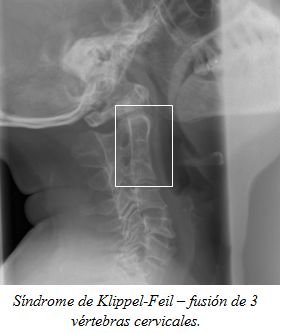

Tortícolis óseos

Varias de las patologías  mencionadas: faringitis, procesos inflamatorios de vía aérea,  puede dar lugar a la laxitud ligamentosa a nivel del atlas, permitiendo deformidad rotatoria y que resulta en tortícolis. La subluxación rotatoria atlantoaxial, es predominantemente una lesión de la infancia, aunque en ocasiones se observa en adultos.

Congénito

Traumático

Inflamatorio

Evaluación radiológica

En condiciones asociadas con subluxación atlantoaxial, (por ejemplo, síndrome de Down, síndrome de Morquio, el síndrome de Larsen, y el síndrome de Marfan), se debe hacer radiografías de la columna cervical.

Después de inmovilización de la columna cervical, deben realizarse radiografías cervicales, en todos los casos con sospecha de traumatismo cervical.